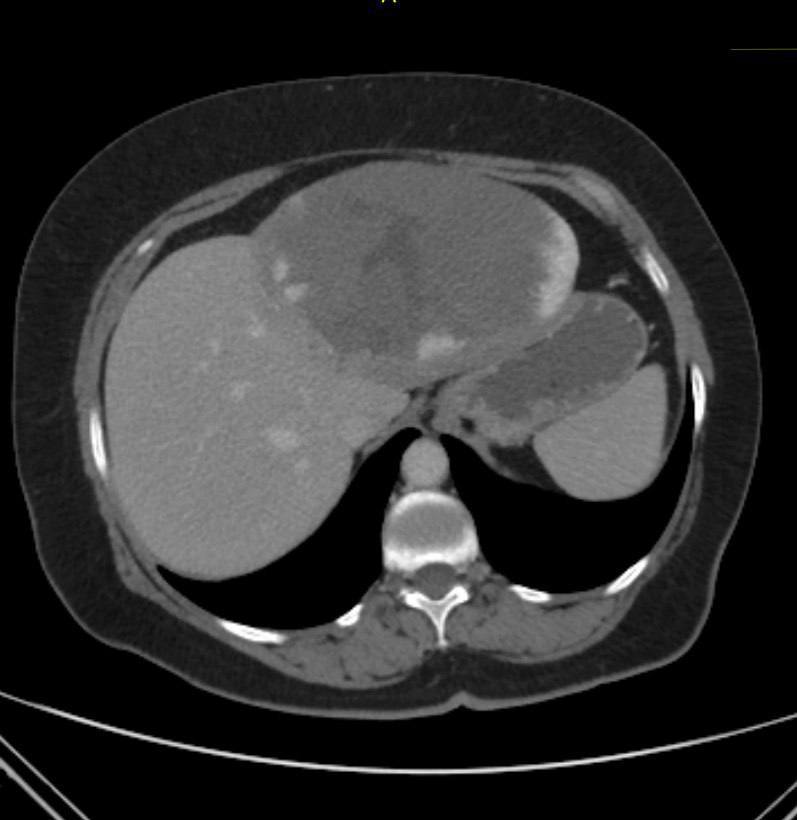

Пухлину рекордних розмірів видалили хірурги Рівненського обласного протипухлинного центру. Йдеться про гемангіому печінки, розмір якої за рік збільшився від 4 до 15 см. Видалили її 64-річній пацієнтці. Складне оперативне втручання, яке має назву лапароскопічна лівобічна гемігепатектомія, провели хірурги-онкологи Маргарита Пісецька, Андрій Валяєв та Павло Рябошапко.

Як пояснили в обласному протипухлинному центрі, гемангіома є найпоширенішою доброякісною пухлиною печінки. Її виявляють у 2–20% населення. Зазвичай такі пухлини мають розмір 3-5 см і не ростуть. Також здебільшого не провокують симптомів та не потребують лікування.

А от утворення більші за 5 см фахівці відносять до гігантських гемангіом. В історії є випадки видалення таких пухлин. До прикладу, львівські хірурги видалили пухлину завбільшки 10 см.

Тому клінічний випадок в історії рівненських онко-хірургів можна вважати справді унікальним.